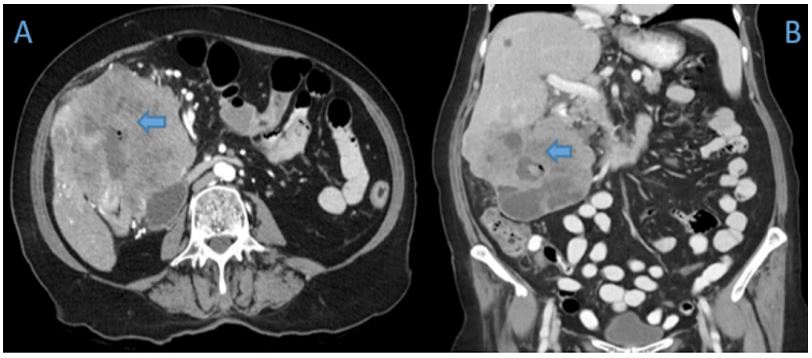

A 70-year old female was referred to the emergency department of a tertiary hospital by her general practitioner with a sixmonth history of lethargy, six-kilogram weight loss and vague right sided abdominal pain. She denied vomiting, altered bowel habit or rectal bleeding. Her relevant surgical history included cholecystectomy and thyroidectomy. There was no family history of colorectal cancer. Pertinent examination findings included a soft, non-distended abdomen with a large non-mobile palpable mass in the right upper quadrant. Her blood profile included leukocytosis (12.9 x109 /L), anaemia (Hb 79 g/L), normal bilirubin and mildly deranged liver function tests. Furthermore, she had a markedly raised CA 19.9 (5506 kU/L) and CEA (462.1 microg/L). She was admitted for a blood transfusion and further investigations. A triple phase computed tomography scan of the chest, abdomen and pelvis revealed an 11x10x10.5 cm hepatic flexure mass with invasion into the right hepatic lobe (Figure 1). Surprisingly, there was no evidence of colonic obstruction, nor distant metastatic disease. A colonoscopy demonstrated a large circumferential, fungating and partially obstructing mass extending into the ascending colon (Figure 2). Biopsy confirmed a poorly differentiated invasive adenocarcinoma (Figure 3). Following discussion at a multi-disciplinary surgical oncology meeting, she proceeded to an ileo-colonic bypass with planned adjuvant chemotherapy. Intra-operatively, the mass was invading the liver, with small amounts of ascites and no peritoneal metastasis. Proximal small and large bowel were of normal caliber. An ileo-colic side-to-side anastomosis was performed using the distal ileum and mid transverse colon. The patient made an uneventful recovery and was discharged day four post operatively with medical oncology follow up.

Figure 1: Axial (A) and coronal (B) computed tomography images of the hepatic flexure neoplasm (Blue arrow) invading the right liver lobe.